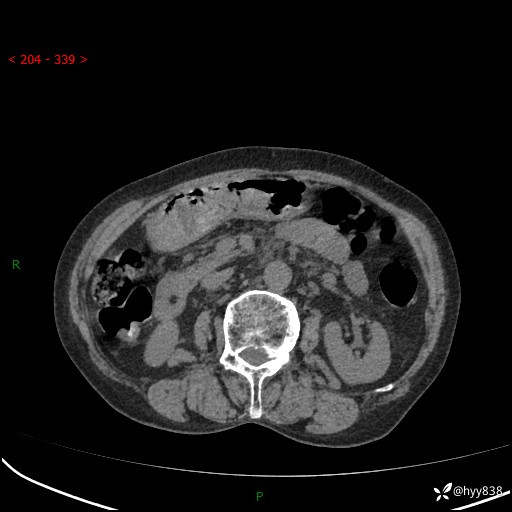

全腹部CT平扫